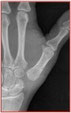

Le diagnostic repose sur la clinique. Les radiographies de face et de profil de l’articulation trapézo-métacarpienne (T-M) sont nécessaires pour confirmer le diagnostic, établir le stade de l’arthrose et dans certains cas faire le diagnostic différentiel avec l’arthrose péritrapézienne qui peut toucher toutes les surfaces articulaires du trapèze.